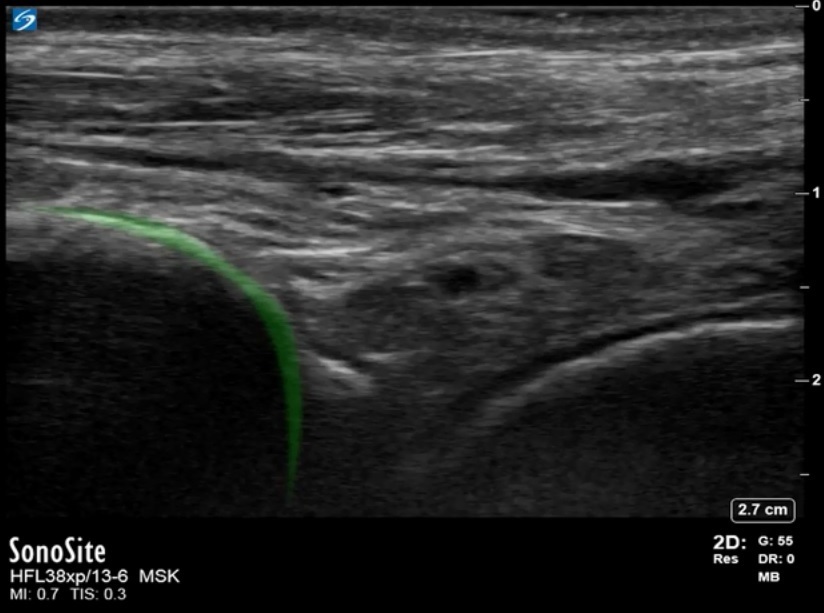

Bild: Fuß und Sprunggelenk, Recessus anterior der Tibia

Markierter Bereich: Tibia